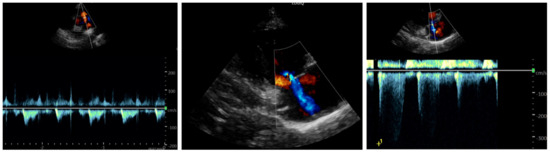

Background and Clinical Significance: Scurvy, caused by chronic vitamin C deficiency, is re-emerging in Western countries, particularly among pediatric patients with highly selective diets. While its musculoskeletal and mucocutaneous manifestations are well-known, its association with pulmonary arterial hypertension (PAH) is rare and poorly understood. Ascorbic acid and iron are essential cofactors for prolyl hydroxylases (PHD), which regulate Hypoxia-Inducible Factors. Their combined deficiency may trigger a “pseudohypoxic” state, leading to pulmonary vascular remodeling and vasoconstriction. Case Presentation: A 30-month-old female presented with a one-month history of limping, lower limb pain, and gingival hypertrophy. Dietary history revealed an almost exclusive cow’s milk-based intake. Physical examination showed diffuse petechiae, pallor, and right knee edema. Laboratory findings confirmed scurvy (undetectable vitamin C), severe iron-deficiency anemia (Hb: 72 g/L; ferritin: 22 mcg/L; RDW: 30%), folate deficiency, and hyperhomocysteinemia. Notably, elevated copper and vitamin B12 levels suggested a state of metabolic dysregulation. Echocardiography revealed moderate PAH phenotype (estimated sPAP: 47–50 mmHg) and a hyperdynamic contractility. A “perfect storm” mechanism was hypothesized, involving iron–ascorbate-dependent PHD impairment, high-output state, and oxidative-stress-induced hepcidin dysregulation (suggested by elevated copper). Following intravenous vitamin C and multivitamin supplementation, pulmonary pressures normalized within one week. Conclusions: PAH phenotype in scurvy represents a reversible metabolic disruption of pulmonary vascular tone rather than a structural disease. This case underscores the synergistic role of vitamin C, iron, and folate in vascular homeostasis. Clinicians should maintain high suspicion for scurvy in children with selective diets and unexplained PAH, as nutritional restoration is curative. Full article